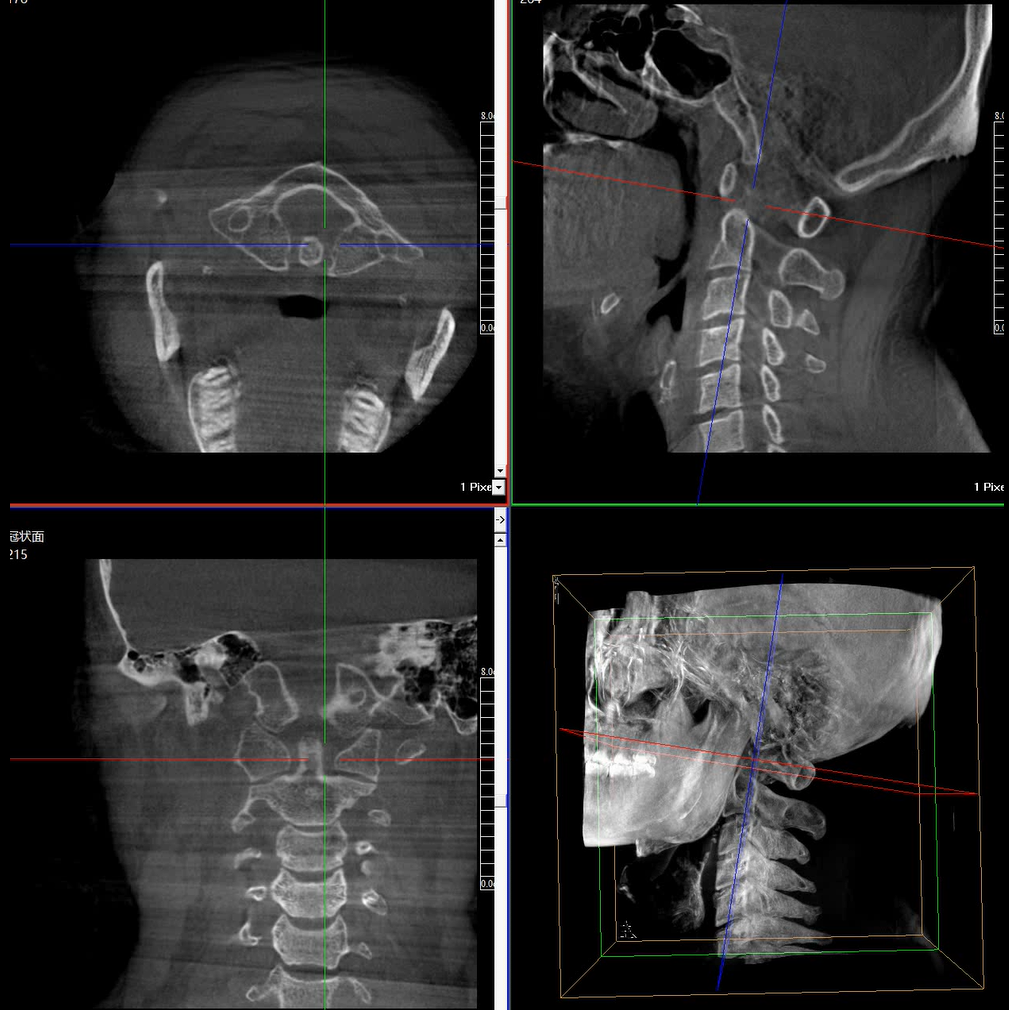

術(shù)中三維成像和橫斷面圖像提供多角度的手術(shù)診斷信息,輔助醫(yī)生進行術(shù)中評估判斷,諸如骨折復(fù)位情況和內(nèi)植入螺釘?shù)某叽绾臀恢?,輔助手術(shù)更好地完成。

提供更大的術(shù)中三維成像視野,采集更多圖像信息,可一次拍全全段頸椎、全段腰椎、七節(jié)胸椎、雙側(cè)骶髂關(guān)節(jié)、股骨頭及單側(cè)盆骨。